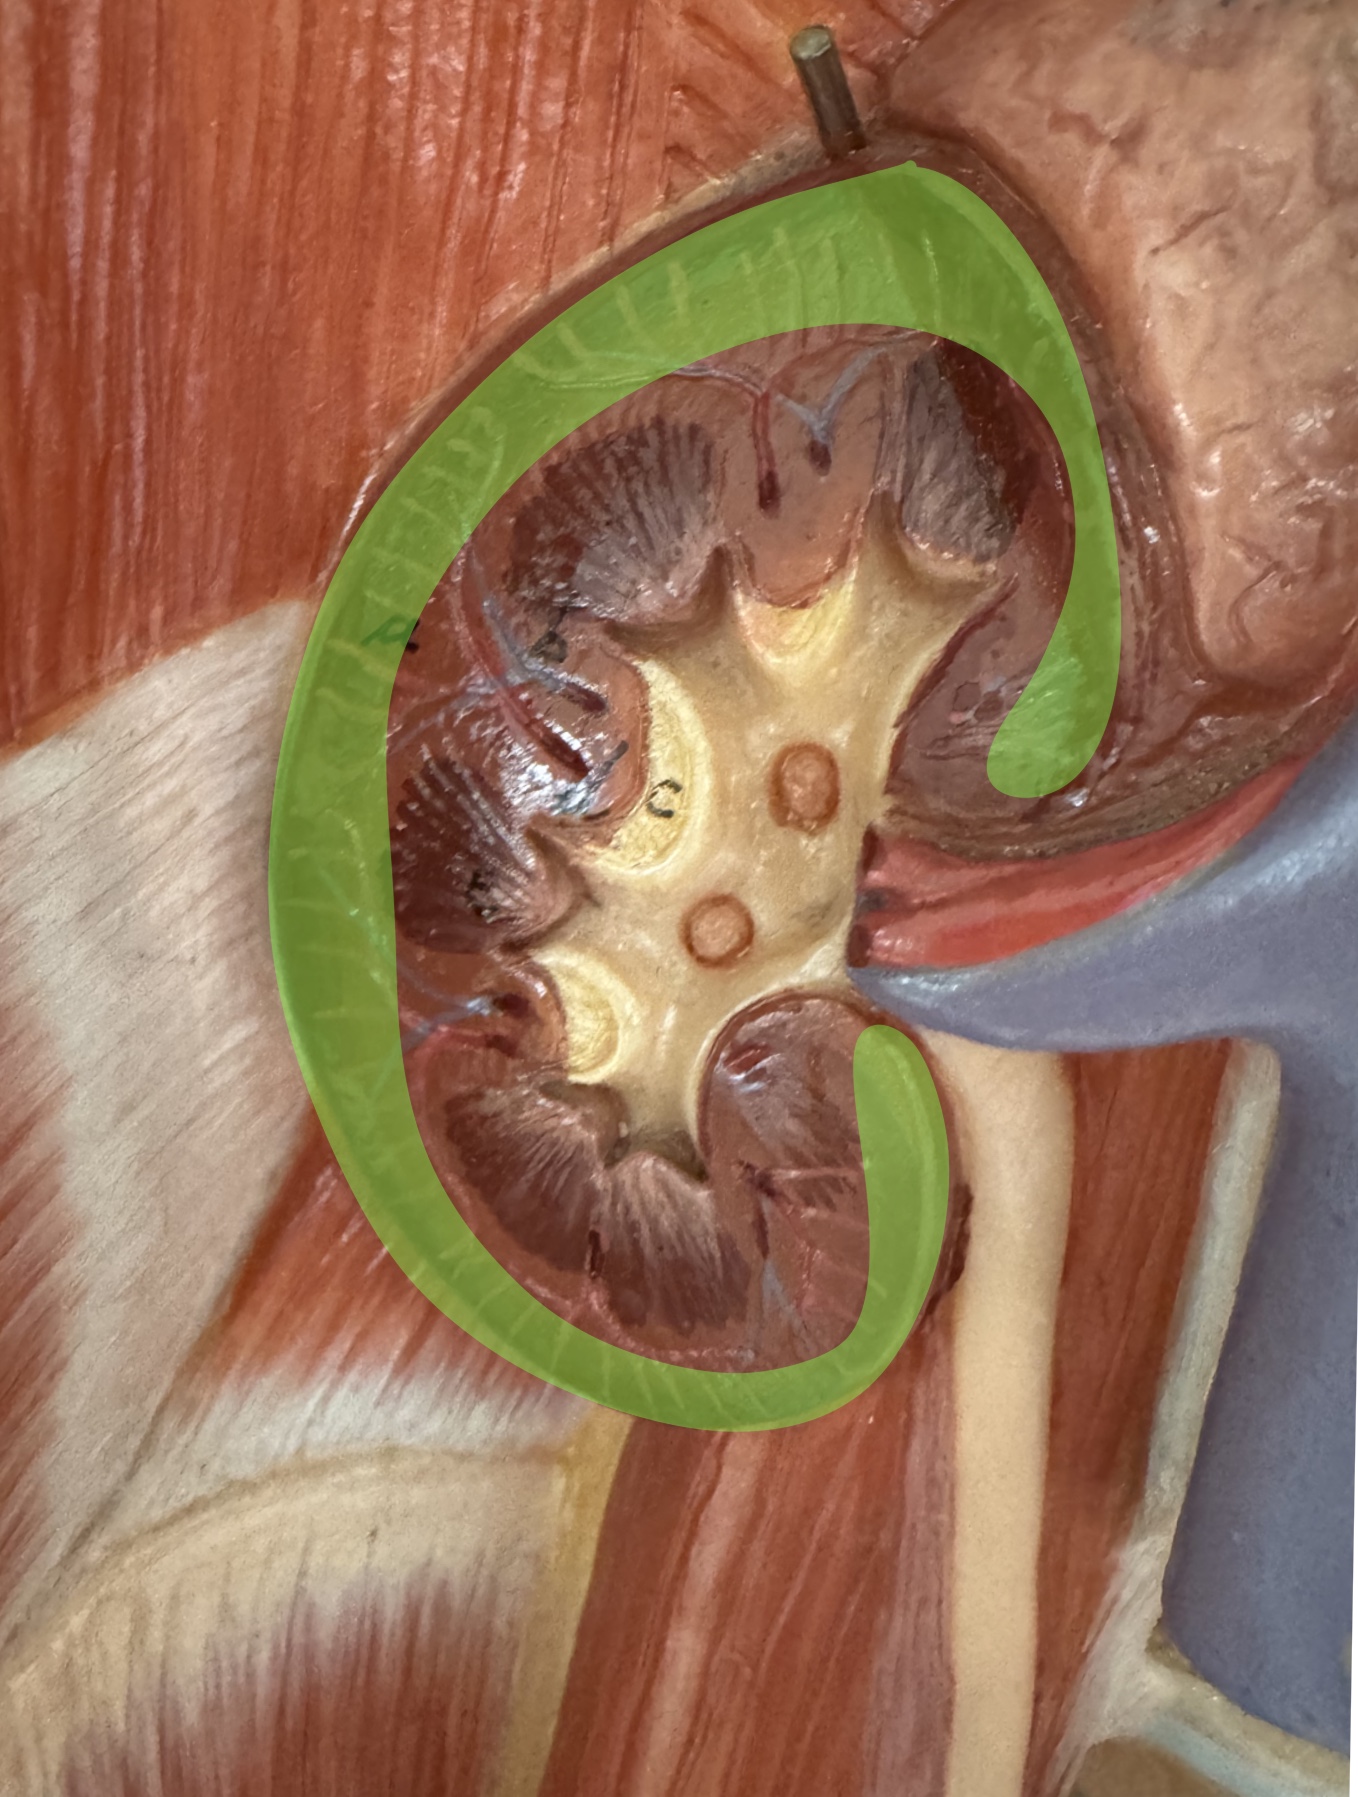

What is the picture of?

Kidney cortex

What is this structure

Nephron

What are these parts of the nephron?

Glomerular capsule with glomerulus

Proximal convoluted tubule

Nephron loop

Distal convoluted tubule

Collecting duct

Peritubular capillaries